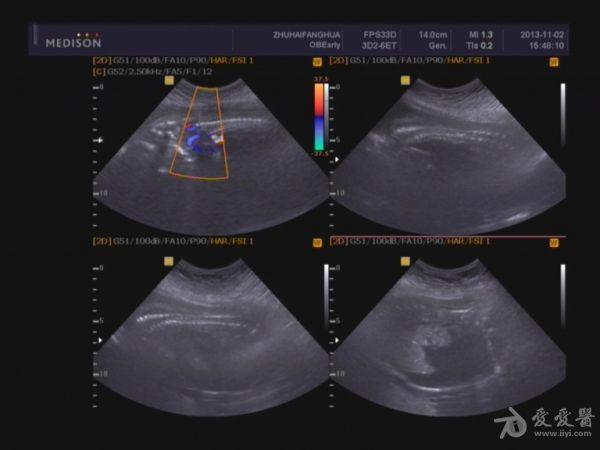

胎盘:附着于子宫后壁,厚度44mm,成熟度:0级,范围面积大,几乎覆着全后壁。

脐带:结构正常,脐动脉血流参数:SPV:33cm/s,PI:1.0,RI:0.62,S/D:2.6。典型图片如下: